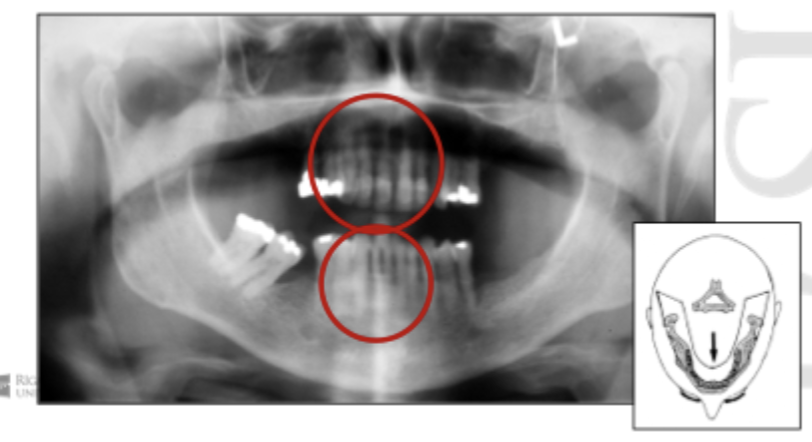

Patient position - Antero-posterior error

Patient too forward, too close to film. Teeth narrowed.

Patient too backwards, too far away from film. Teeth magnified & widened.